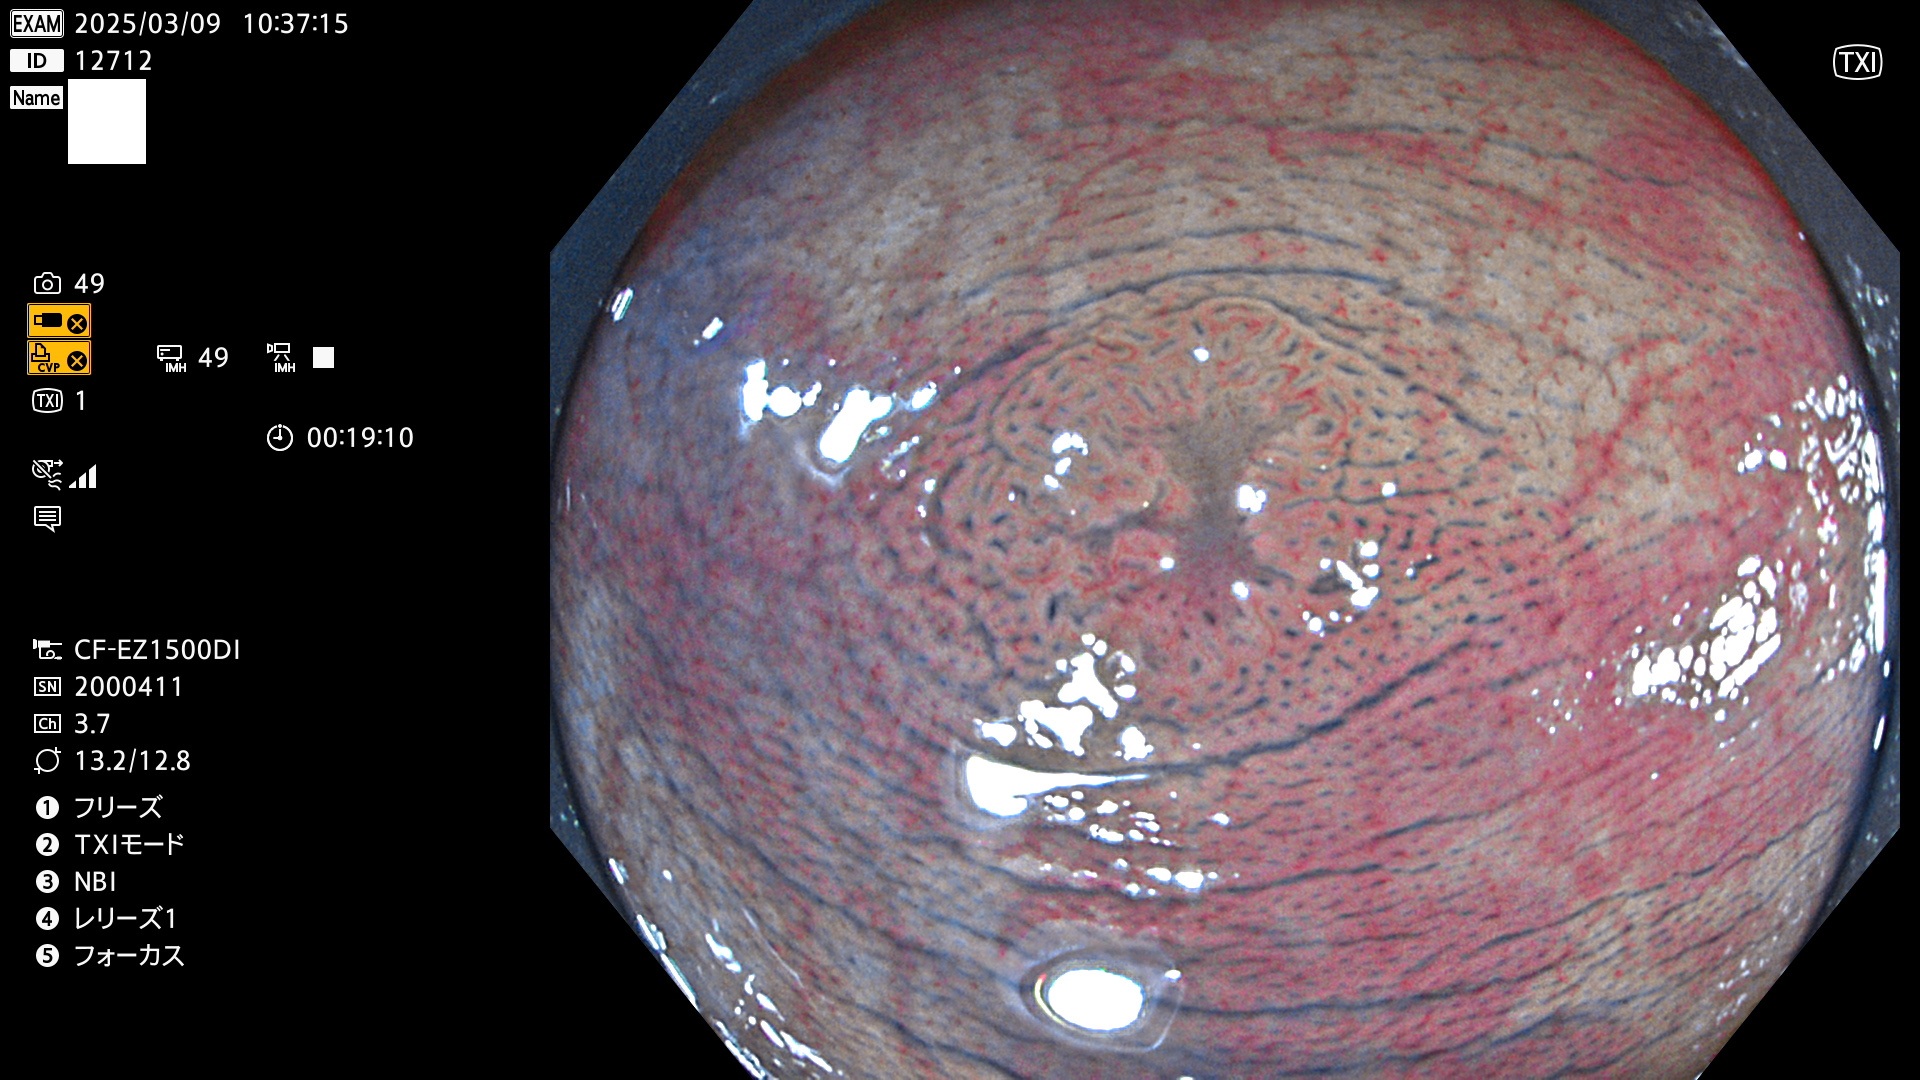

今週のUb、Uc型腺腫

完全に平坦な物をUb、陥凹している物をUcと呼びます。最も発見が難しく危険な病変です。

毎週の検査(木・金・土・日)に発見されたUb、Uc型・腺腫を、その週の日曜の夜にUPし1週間、提示します。

抽出の対象期間 2025年3月6日〜3月9日の4日間(48件の検査)5個 (5/48=10%)